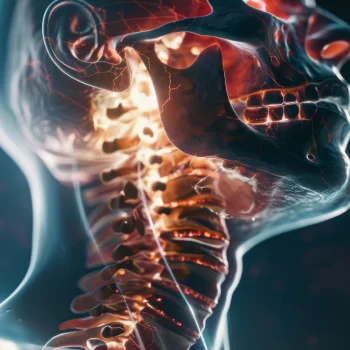

در این روش تصویر برداری یک صفحه (گیرنده یا دتکتور) در زیر عضو و قسمت مورد نظر قرار داده می شود و اشعه ایکس(دُز از اشعه جهت تشخیص) به همان قسمت که روی صفحه قرار گرفته تابنده می شود و توسط صفحه اطلاعات دریافت می شوند و همین اطلاعات پس از پردازش های لازم در نهایت عکس رادیولوژی به ما ارائه می دهد. کاربردهای رادیولوژی در منزل دقیقاً همان کاربرد رادیولوژی در بیمارستان ها می باشد از جمله بررسی انواع شکستگی ها، دررفتگی مفاصل، آرتروز مفاصل، دیدن پروتز های داخل استخوان از نظر بررسی موقعیت پروتز، آب آوردگی ریه(اِدم وافیوژن) و عفونت ریه، شکستگی دنده ها، انساد و وجود هوا در شکم و… می باشند. رادیولوژی در منزل تمام این خدمات را ارائه می دهد.

تصاویری از رادیولوژی در منزل توسط گاما پرتو